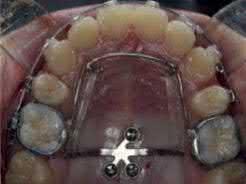

1.1  Class III correction with TADs and sliding jigs [7]. (a) Initial examination indicated full-step Class III canine and molar relationships. (b) TADs were placed and connected with a sliding jig. (c) Schematic illustration shows a miniscrew-anchored sliding jig and the direction of the force. (d) Final examination indicated Class I canine and molar relationships. Source: Tai et al. [7]. Reprinted with permission from Elsevier.

(a)

(b)

(d)

(c)

Figure